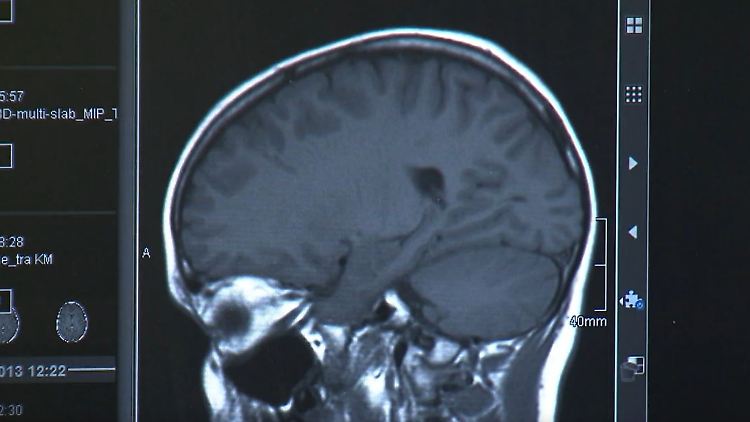

Schlafapnoe schadet GehirnNächtliche Atemaussetzer erhöhen Parkinson-RisikoWenn nachts die Atmung stoppt, bleibt das nicht ohne Folgen: Forschende finden nun heraus, dass unbehandelte Schlafapnoe das Parkinson-Risiko deutlich erhöht. Es gibt allerdings eine einfache Möglichkeit, sich zu schützen.25.11.2025